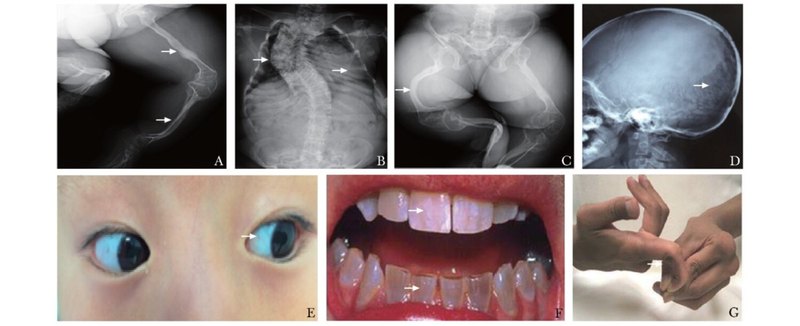

一、問:有一種寶寶被人稱為“瓷娃娃”,您能給大家介紹一下這是什么樣的寶寶嗎?姜海:大家好,“瓷娃娃”是患成骨不全癥的兒童,形容患兒骨骼像瓷器一樣容易摔碎,輕微的外力即可引起四肢骨折,嚴重的病例咳嗽,翻身等簡單的日常行為都有可能引起肋骨骨折,脊柱骨折。該病是最常見的單基因遺傳性骨病,以骨量低下、骨骼脆性增加和反復骨折為主要特征。該病已列入國家衛(wèi)生健康委員會等5部門聯(lián)合制定的《第一批罕見病目錄》。二、問:哦,這是一種病,名稱叫“成骨不全癥”,還是罕見病。既然罕見,那這種患病的寶寶應該不多吧。姜海:該病雖然為罕見病,它的發(fā)病率新生兒在一萬五至兩萬分之一。但中國的新生兒一年的數(shù)量巨大。2021年中國的新生兒為1062萬,按照這個患病率,2021年可能的成骨不全癥兒童有大約708至531人。十年下來,中國的成骨不全癥兒童應該有五千至一萬人左右。三、問:那這個病是怎么得得了?是和父母有遺傳關系嗎?姜海:該病是由多種致病基因突變所致。目前已報道的致病基因至少有21種。其遺傳模式只要呈常染色體顯性遺傳。有可能父母各攜帶一個突變基因,父母不發(fā)病,生出來的寶寶結合了父母的兩個突變基因,就發(fā)病了。也有可能父母都是正常的,僅是寶寶在發(fā)育過程中出現(xiàn)了基因的突變導致發(fā)病。四、問:這個病有什么臨床表現(xiàn)?作為父母,如何能早期發(fā)現(xiàn)寶寶患了這個???姜海:成骨不全癥常幼年發(fā)病,輕微創(chuàng)傷后反復發(fā)生骨折,病情嚴重者在宮內或出生時即骨折,可導致脊柱側凸,胸廓塌陷,四肢彎曲等畸形。患兒還可伴有聽力下降,關節(jié)韌帶松弛,心臟瓣膜病變等骨骼外表現(xiàn)。該病危害大,具有較高的致殘率。作為父母,如果發(fā)現(xiàn)寶寶輕微外力下就容易骨折,同時一年內多次骨折,一定要警惕患這種病。同時注意觀察寶寶的鞏膜,看是否鞏膜是藍色的?;颊叩湫蚗線表現(xiàn)及常見體征如箭頭所示,A:長骨纖細,皮質菲薄,多發(fā)陳舊性骨折;B:脊柱側凸畸形,胸郭塌陷;C:骨盆畸形,長骨彎曲畸形;D:顱板薄,枕骨縫間骨;E:藍鞏膜;F:牙本質發(fā)育不全;G:指間關節(jié)韌帶松馳;五、問:如何來確診寶寶患了這個病呢?姜海:主要依據(jù)臨床表現(xiàn)和影像學特點,包括自幼發(fā)病,反復脆性骨折史;藍鞏膜;聽力下降;陽性骨折家族史;骨骼X線影像特征。此外,應注意排除多種遺傳性及代謝性骨骼疾病,如軟骨發(fā)育不全、低血磷性佝僂病、維生素D依賴性佝僂病、骨纖維異樣增殖癥、低磷酸酶血癥、腫瘤相關骨病和關節(jié)活動過度綜合征等?;蛟\斷對發(fā)現(xiàn)該病的病因、做好遺傳咨詢和優(yōu)生優(yōu)育具有積極意義。由于尚未發(fā)現(xiàn)呈成骨不全癥的所有致病基因,因此基因診斷不能代替臨床診斷,基因檢測陰性者不能完全排除罹患該病的可能。有生育需求的成骨不全癥患者或已育有成骨不全癥患兒的夫婦擬再生育者,建議行基因診斷,為遺傳咨詢和產前基因診斷做準備。目前成骨不全癥的產前診斷需通過羊膜穿刺獲得胎兒基因組DNA樣本。羊膜穿刺有3個時機:妊娠第11~13周取絨毛組織;或妊娠第16~24周取羊水細胞;或妊娠第23周后取臍血。建議選擇有條件的醫(yī)院婦產科行羊膜穿刺,盡早獲得胎兒基因組DNA樣本,進行基因診斷。六、問:目前這個病能治愈嗎?該如何治療?姜海:該病目前還不能完全治愈,但通過綜合性的治療,可以改善患兒的活動能力,提高生活質量。適量的鈣劑和維生素D有助于提供骨骼發(fā)育所需的營養(yǎng)。目前廣泛使用的治療成骨不全癥的藥物主要是雙膦酸鹽類。雙膦酸鹽屬于骨吸收抑制劑,能夠與骨骼羥基磷灰石結合,有效抑制破骨細胞活性,減少骨吸收,從而增加骨密度,降低骨折風險。第二代帕米膦酸二鈉,第三代唑來膦酸臨床運用治療成骨不全癥兒童安全性較好。兒童一旦確診成骨不全癥,應當盡早給予雙膦酸藥物治療,能增加患兒的骨密度,降低骨折風險,改善疾病預后。西北婦女兒童醫(yī)院骨科已采用第二代帕米膦酸二鈉靜脈輸液治療成骨不全癥兒童數(shù)年,具有良好的安全性,臨床效果滿意。通過治療后,患兒的骨密度明顯增強,不再容易發(fā)生骨折,打破了以往的“骨折-臥床-骨質疏松加重-再骨折”的惡性循環(huán),減輕了患兒的痛苦和家庭的負擔。今年科室開展了第三代唑來膦酸注射液治療成骨不全癥兒童,輸液時間明顯縮短,住院時間也進一步縮短,花費更低,具有良好的臨床推廣價值。